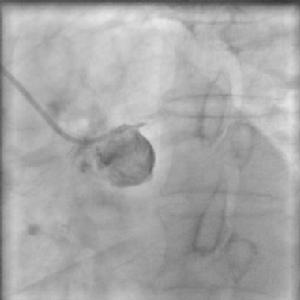

1支或2支腎動脈慢性閉塞可導致腎血管性高血壓。如發現血漿腎素水平增高,特別在套用卡托普利以後提示該診斷的可能性。靜脈腎盂造影病側腎臟較小,造影劑排空延遲;放射性腎圖亦示兩側腎灌注和功能不同。腎動脈造影對確定閉塞的解剖位置是重要的。分側測定腎靜脈腎素水平可提示來自缺血腎的靜脈血中腎素活性增高。